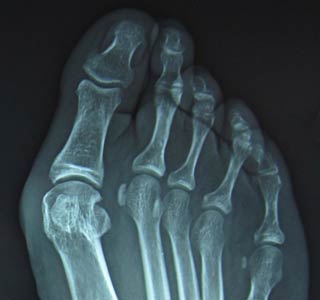

Take a look at our foot health blog about bunions where we explore causes and treatments of bunions including the health benefits of wide toe box shoes.